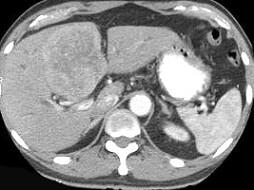

问题 原发性肝癌的临床表现不包括下列哪项 ( )

选项 A、红细胞增多症 B、嗜酸性细胞增多症 C、肝昏迷 D、低血糖症 E、上消化道出血

答案 B